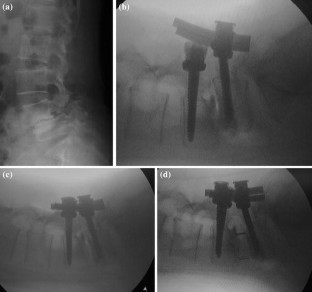

Fig. 1